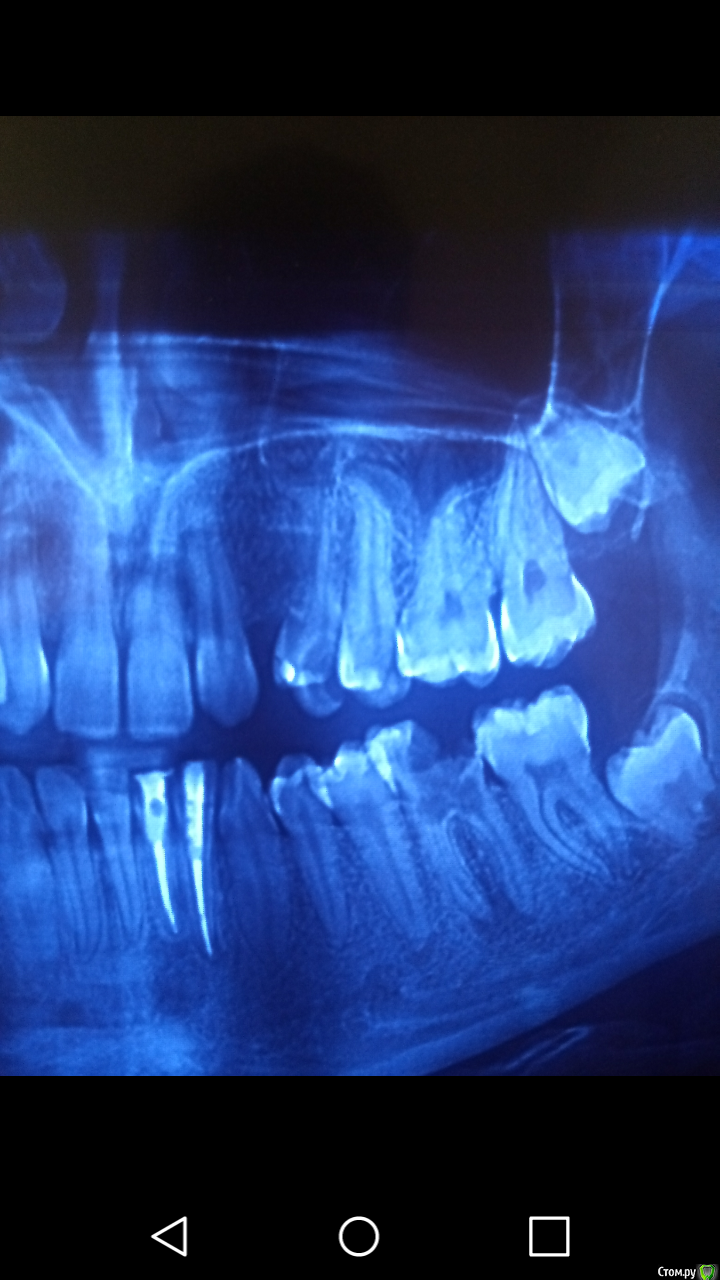

___49___ Опубликовано 28 ноября, 2019 Поделиться Опубликовано 28 ноября, 2019 Здравствуйте! Подскажите как лучше восстановить 3.6 зуб после эндодонтии? Вкладка + коронка? Прикрепленные изображения В данной клинической ситуации пересадка 8ки в место удаленной 6ки дало бы более прогнозируемый результат (у вас на контрольном снимке уже убегает кость в бифуркации) , тем более что у пациента ростковая зона в 8ке еще не закрыта ... Ссылка на комментарий

DmitrySH Опубликовано 28 ноября, 2019 Поделиться Опубликовано 28 ноября, 2019 Леча такое барахло, тратится время и деньги, которые пригодились бы для сохранения других зубов. Да уж, лучше бы кариесы на 34, 35 убрать 1 Ссылка на комментарий